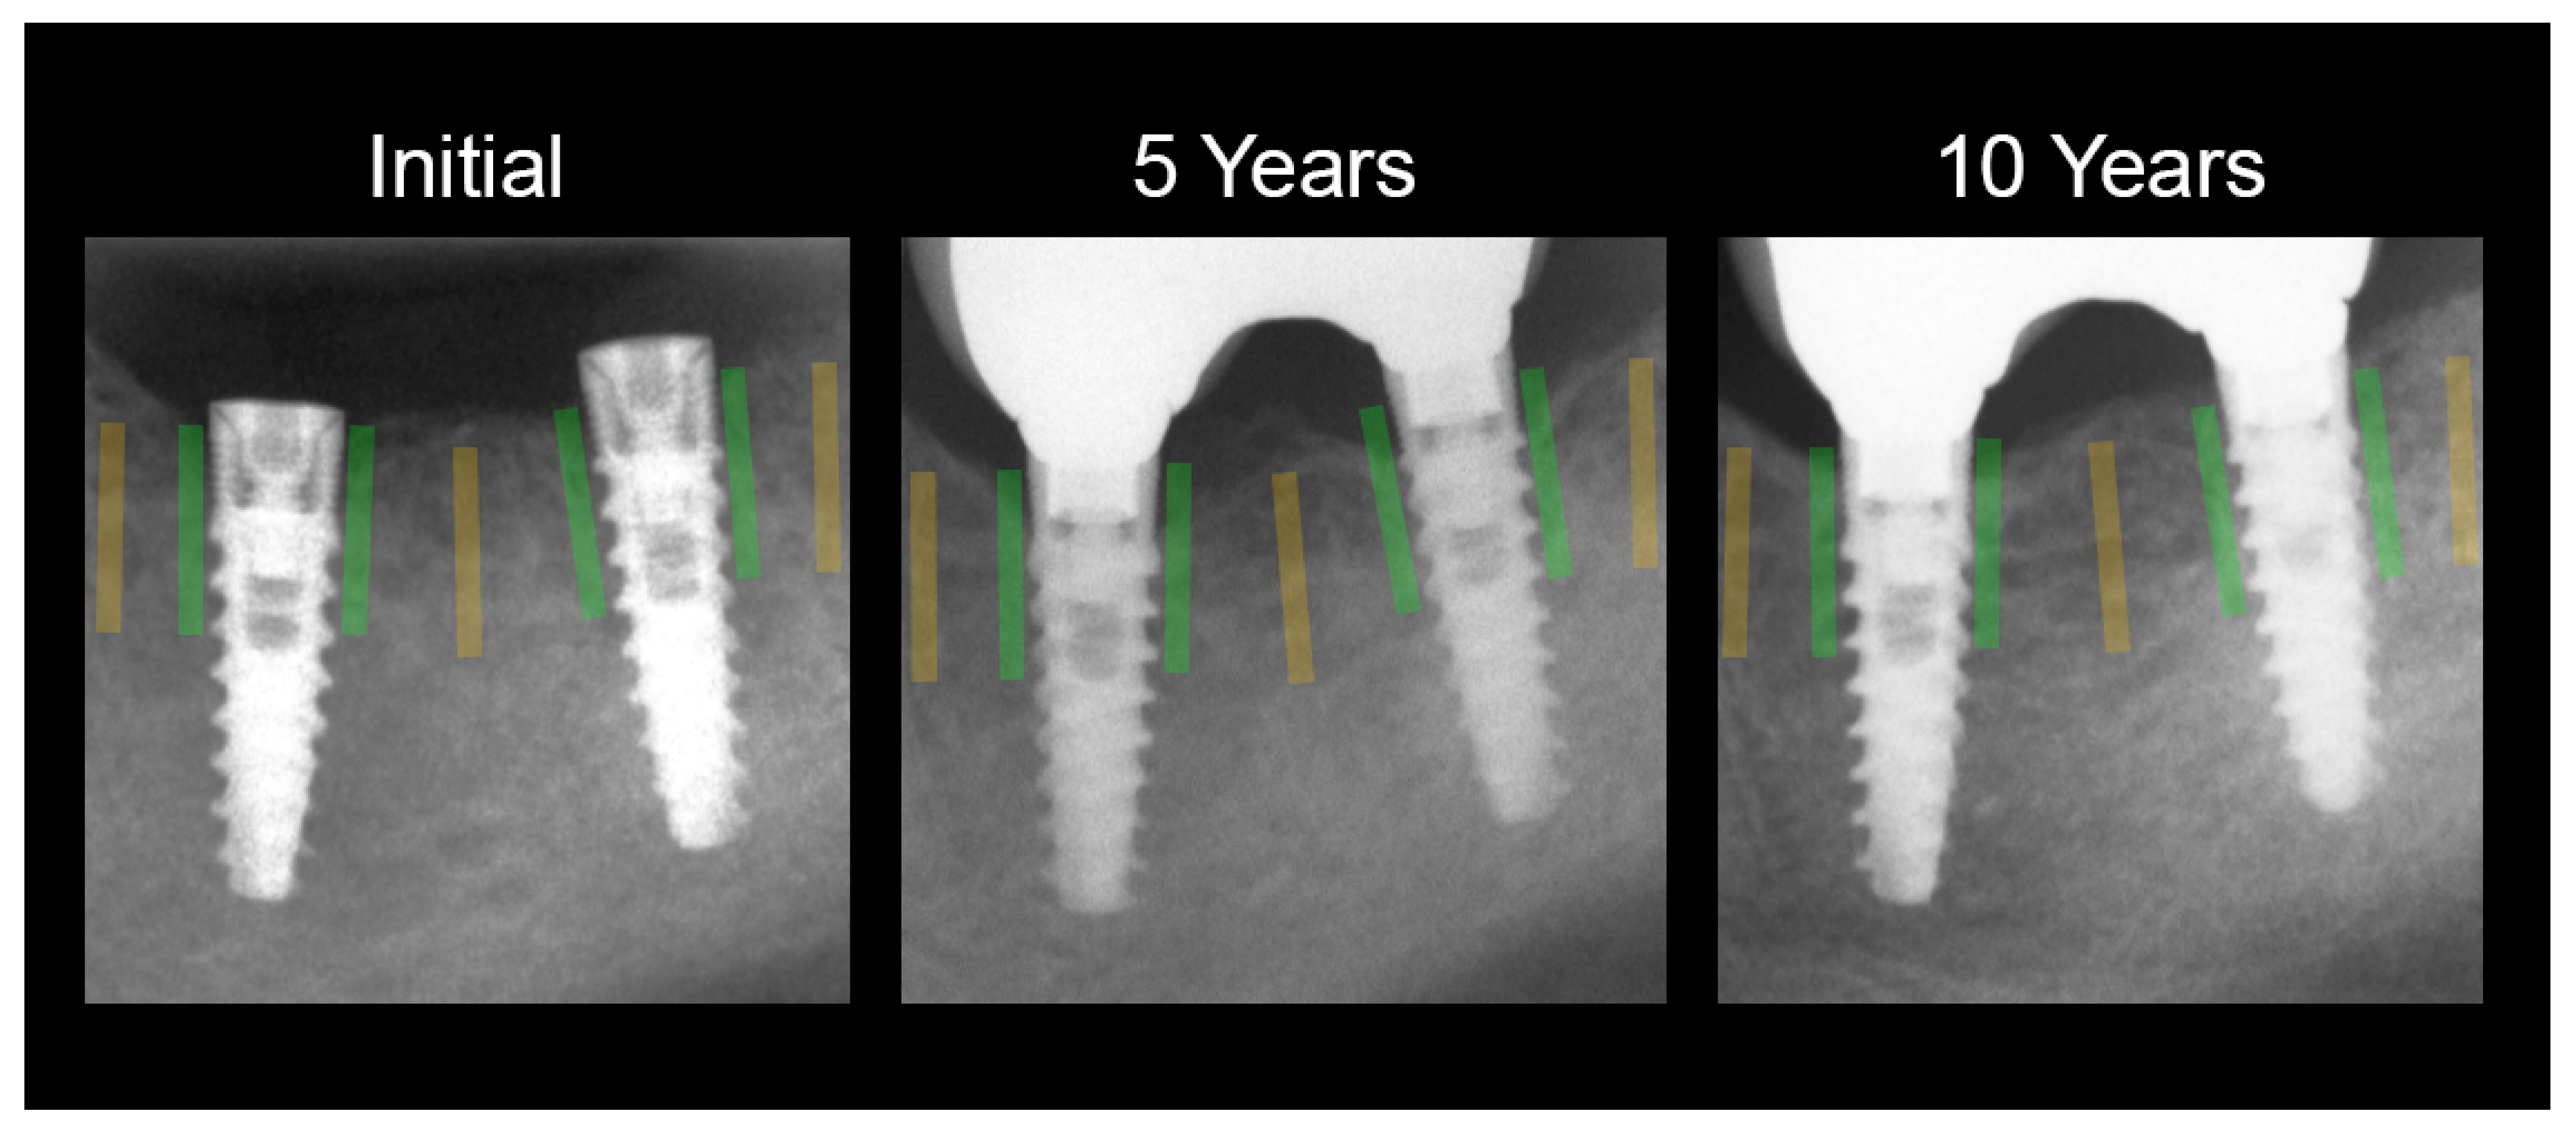

| Reference Cancellous Bone | 149 ± 178 | 0.00 ± 0.00 | n.a. |

| Initial Peri-Implant Observation | 200 ± 146 | 0.25 ± 0.94 | n.s. |

| 5 Years Peri-Implant Observation | 282 ± 182 | 0.83 ± 1.26 | CC = 0.11; R2 = 1.2%; p < 0.001 |

| 10 Years Peri-Implant Observation | 261 ± 168 | 1.48 ± 2.01 | CC = 0.12; R2 = 1,4%; p < 0.01 |